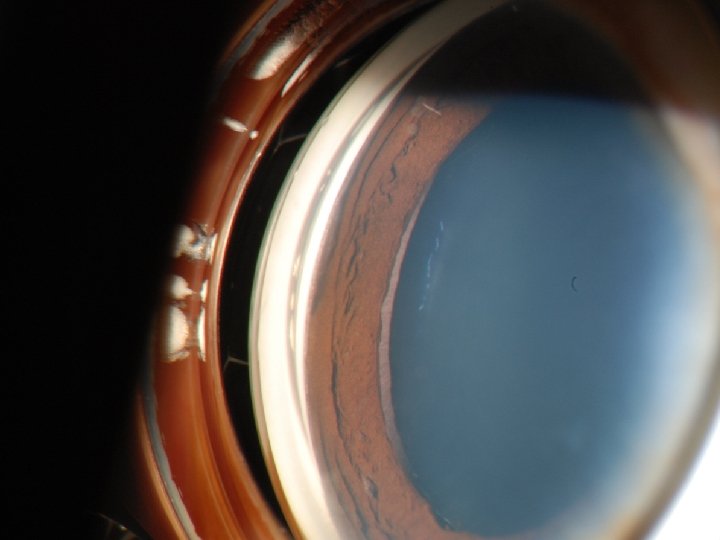

Case n External exam: Unremarkable OU n SLE: n OD: 2+ conjunctival injection; corneal MCE; AC deep & formed with rare cell; multiple iris sphincter tears; lens clear & centered; trace pigmented vitreous cells n OS: Unremarkable n DFE

Diagnosis n Clinical n Gonioscopy n Often small < 4 clock hrs n White band (sclera) below the TM n Ultrasound biomicroscopy (UBM) n Resolution with higher frequencies at the expense of depth of penetration n 50 MHz transducer n 50 μm resolution n 5 mm penetration n Accurate assessment of location & size